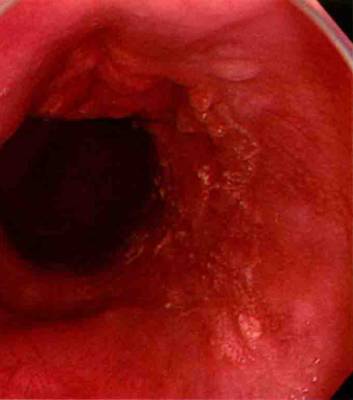

对于白光内镜下发现病变以及高度怀疑存在食管病变的患者,卢戈碘染色是发现食管病变的不可或缺的检查方法,碘染可以显露病变的边界,将病变与正常黏膜区别开来,正常黏膜碘染后呈棕色,炎症、不典型增生等病变存在时,黏膜呈现失染状态,“粉红征”是存在瘤变的特征性表现。

图A显示食管上段黏膜充血水肿,表面粗糙,边界难辨 图B为图A病变碘染后图像,可见较清晰的不染区,呈现典型的“粉红征” 该病变活检后病理为中分化鳞癌

在发现食管某一明显病变时,切勿过分把关注力集中在这一点上,附近的黏膜也要观察清楚,有时候可能会有病变伴随出现

图1:5点方向可见一白色结节状隆起型病变(I型),其周围黏膜白光下似乎没有异常,仔细观察后可发现周围黏膜血管网消失;图2:碘染后可见结节隆起周围黏膜失染(IIb型)